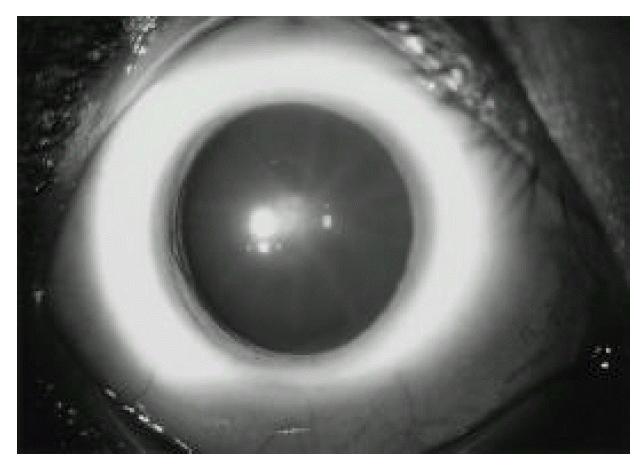

An electrocardiogram revealed no abnormalities except for a sinus tachycardia at a rate of 112. A radiograph of the chest was normal. Both hand AP roentgenogram showed arachnodactyly (Fig. 2). A radiograph of spine showed no scoliosis and kyphosis. An echocardiogram revealed the prolapse of posterior mitral leaflet and mitral regurgitation, but not aortic regurgitation and dissection (Fig. 3). Peripheral blood smear showed markedly increased blasts and decreased platelet count. Findings on bone marrow examination showed that most of the nucleated cells were monoblasts (Fig. 4a) that were negative on myeloperoxidase and chloracetate esterase staining but demonstrated positivity on staining with non-specific esterase (Fig. 4b). Immunophenotype of those cells showed CD13+, CD33+, CD56+ and HLA-DR+. Cytogenetic studies on the marrow showed 46 XY. He was diagnosed as acute monoblastic leukemia (M5a).

Fig. 3.

Echocardiogram (left parasternal long axis view) showing the prolapse of posterior mitral leaflet and mitral regurgitation.